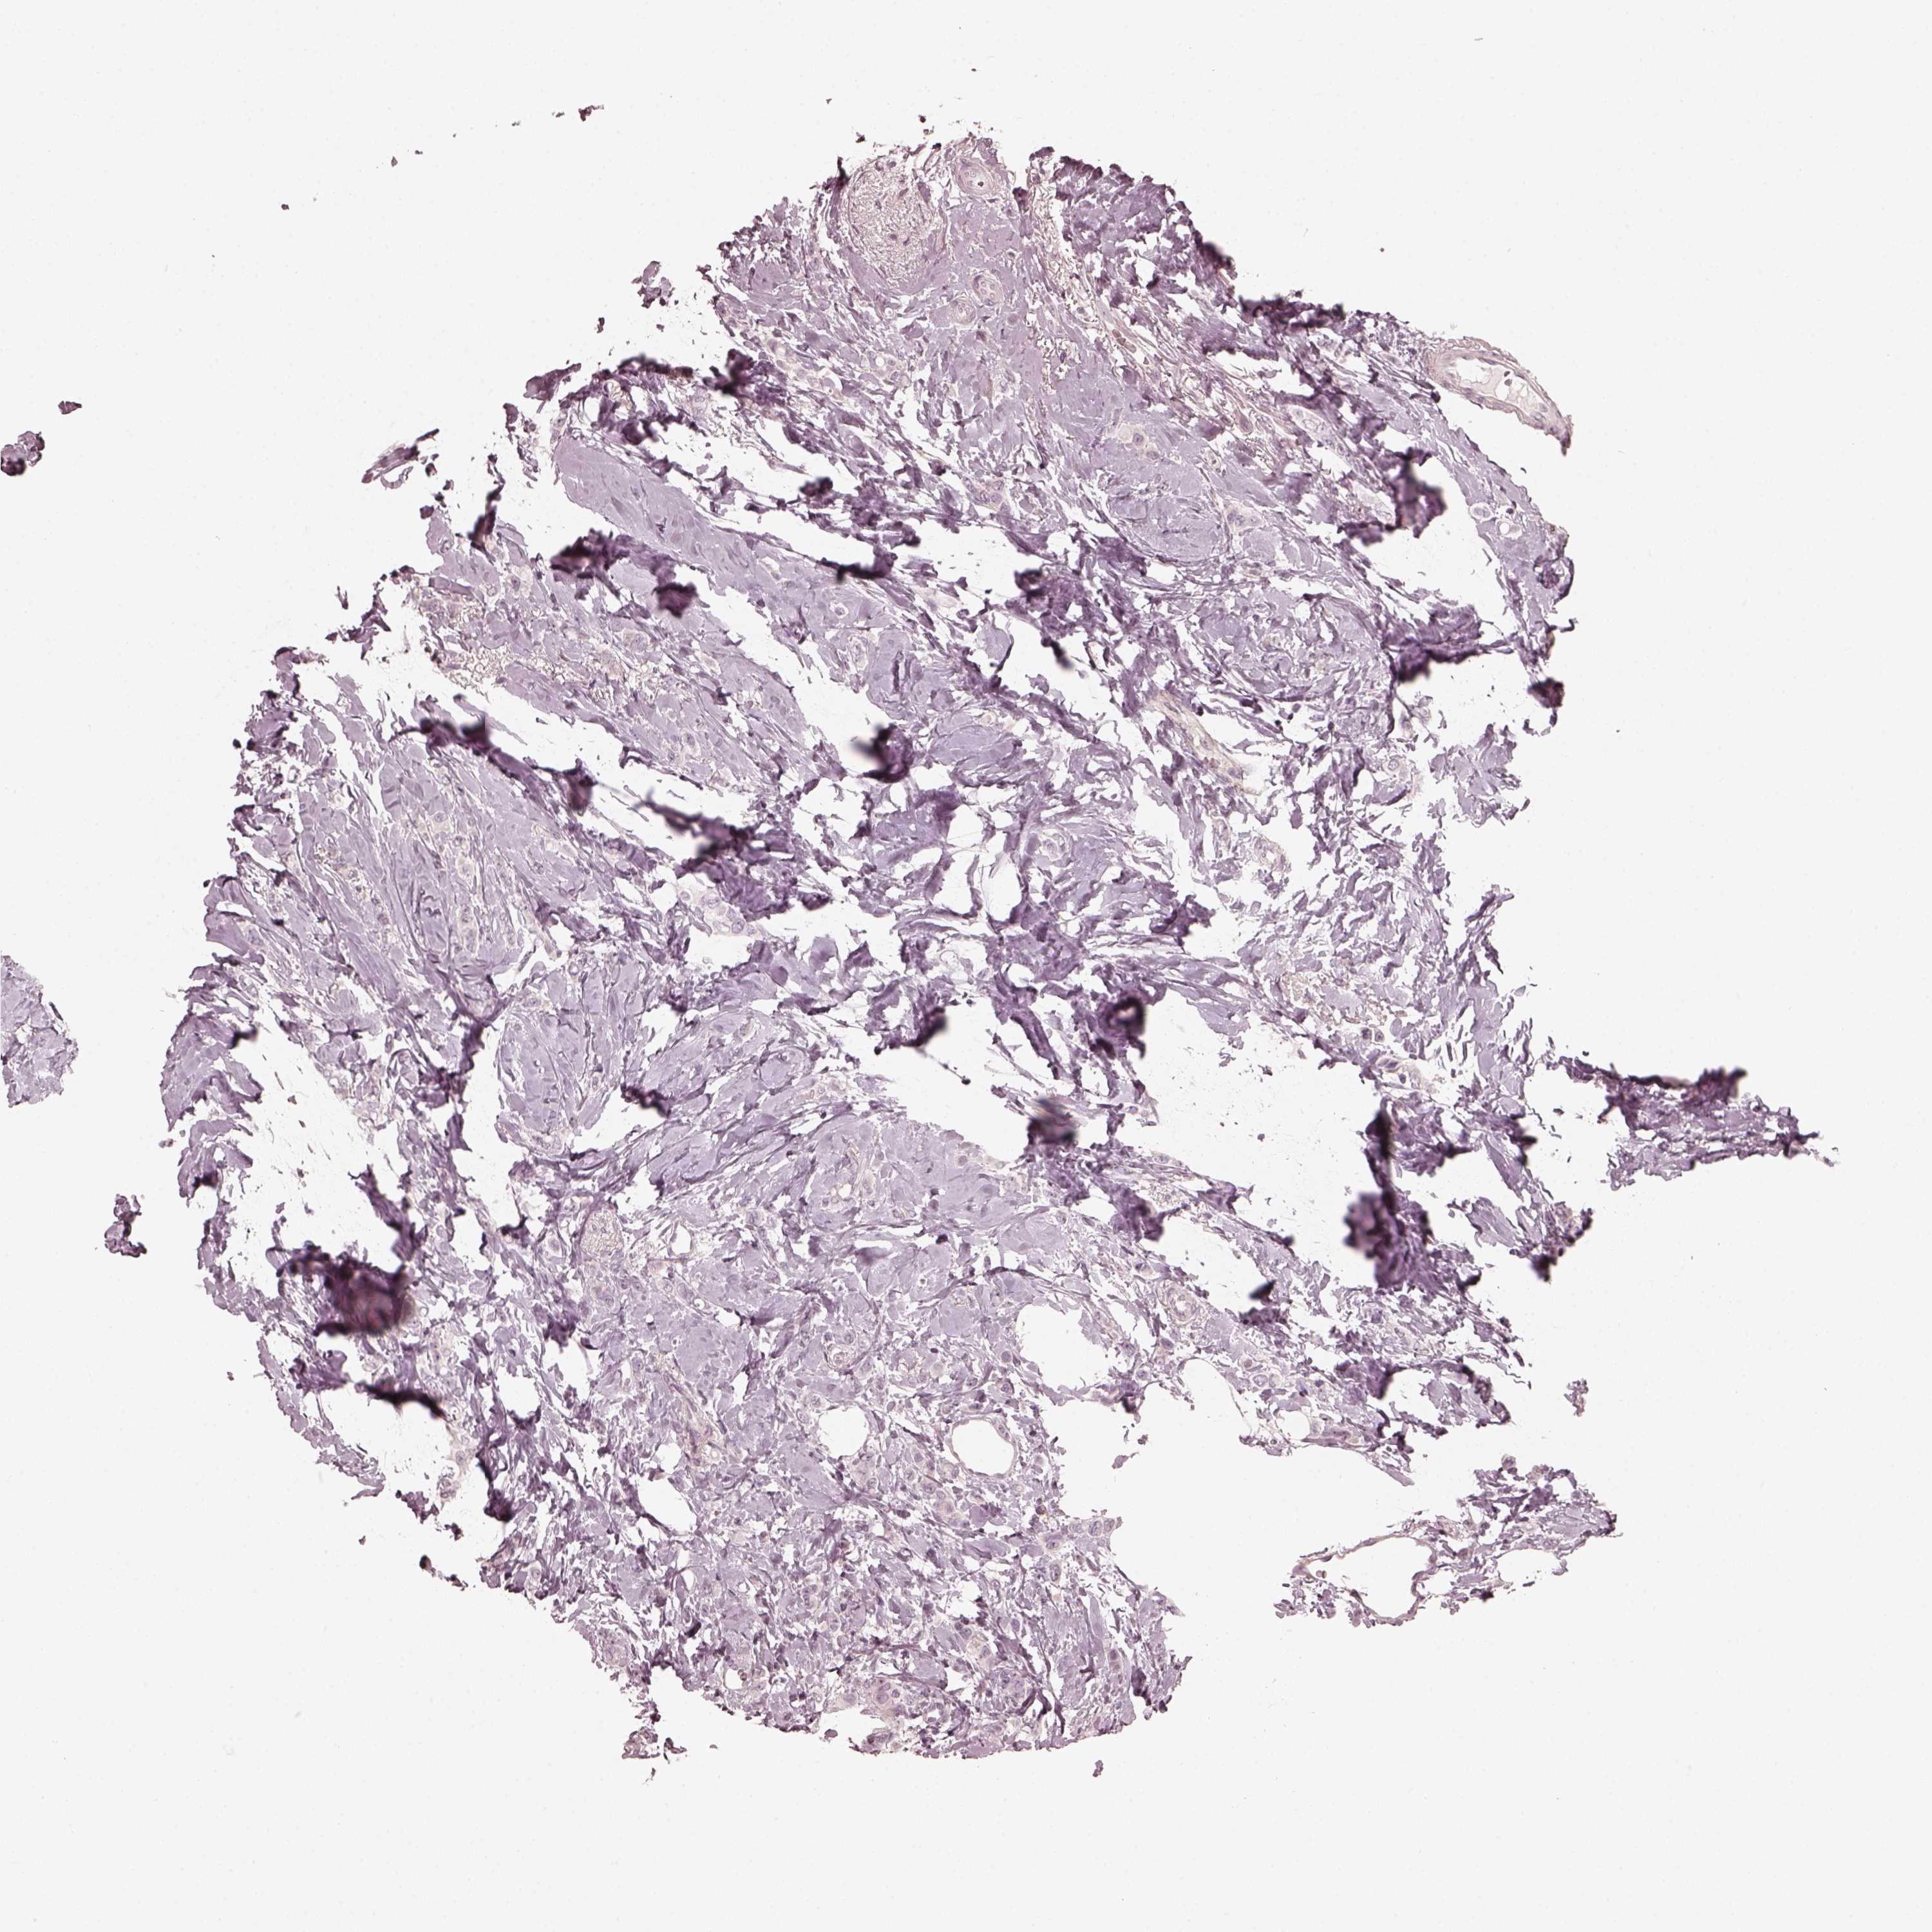

BRCA TCGA BRCA VALIDATION PROTEIN EXPRESSION